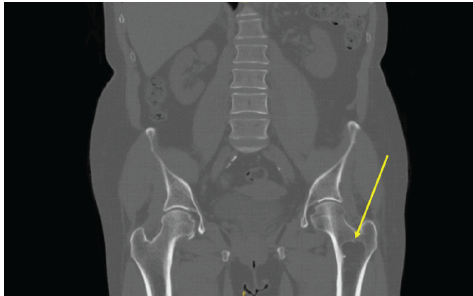

A 64-year-old female presented following a mechanical fall at work, reporting bilateral hip pain, more pronounced on the left side. The patient had no history of hip pain before the fall. Clinical examination demonstrated a preserved range of motion in both hips, with discomfort on weight bearing but no focal neurological deficit. Initial anteroposterior pelvic radiography demonstrated no acute fracture, but revealed a well-defined lucent lesion in the proximal left femur (Fig. 1). A computed tomography (CT) scan of the pelvis was subsequently performed to exclude an occult fracture. CT confirmed an elongated intramedullary lucent lesion within the proximal left femoral metaphysis, characterized by sclerotic margins without cortical destruction, endosteal scalloping, or an associated soft-tissue mass, suggesting a non-aggressive process (Fig. 2 and 3).

Figure 3: Coronal computed tomography of the pelvis demonstrating an elongated, well-defined intramedullary lucent lesion within the proximal left femoral metaphysis (arrow), with sclerotic margins and no cortical destruction or soft-tissue extension, consistent with a non-aggressive lesion.